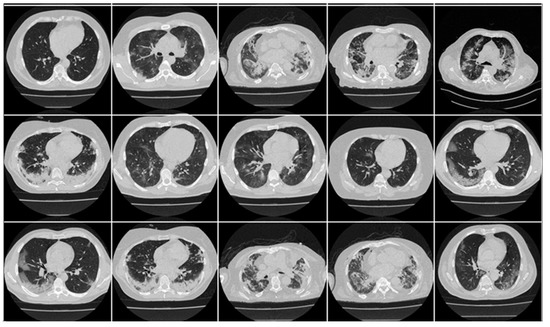

Appendix A includes three figures: Figure A1, Figure A2 and Figure A3. These diagrams are sample images of the dataset. Figure A1 is CroMED (COVID), Figure A2 depicts NovMED (COVID), and Figure A3 shows NovMED (Control).

Figure A1.

Raw “COVID-19 CT slices” taken from CroMED Dataset.

Figure A3.

Raw “COVID-19 CT slices” taken from NovMED dataset.